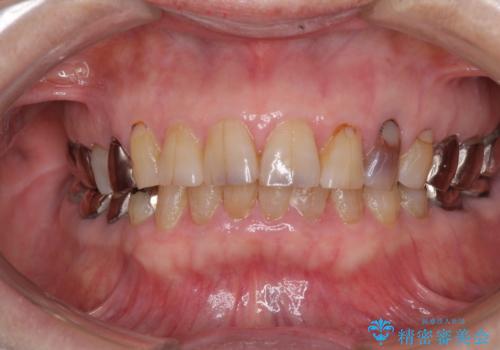

全ての奥歯の銀歯をセラミックに メタルフリー治療

- 奥歯に装着されている銀歯を全て外したいとのことで来院された患者様です。

土台に含まれている金属も含め、奥歯の金属は全て除去し、オールセラミッククラウンやセラミックインレーにて治療することとしました。